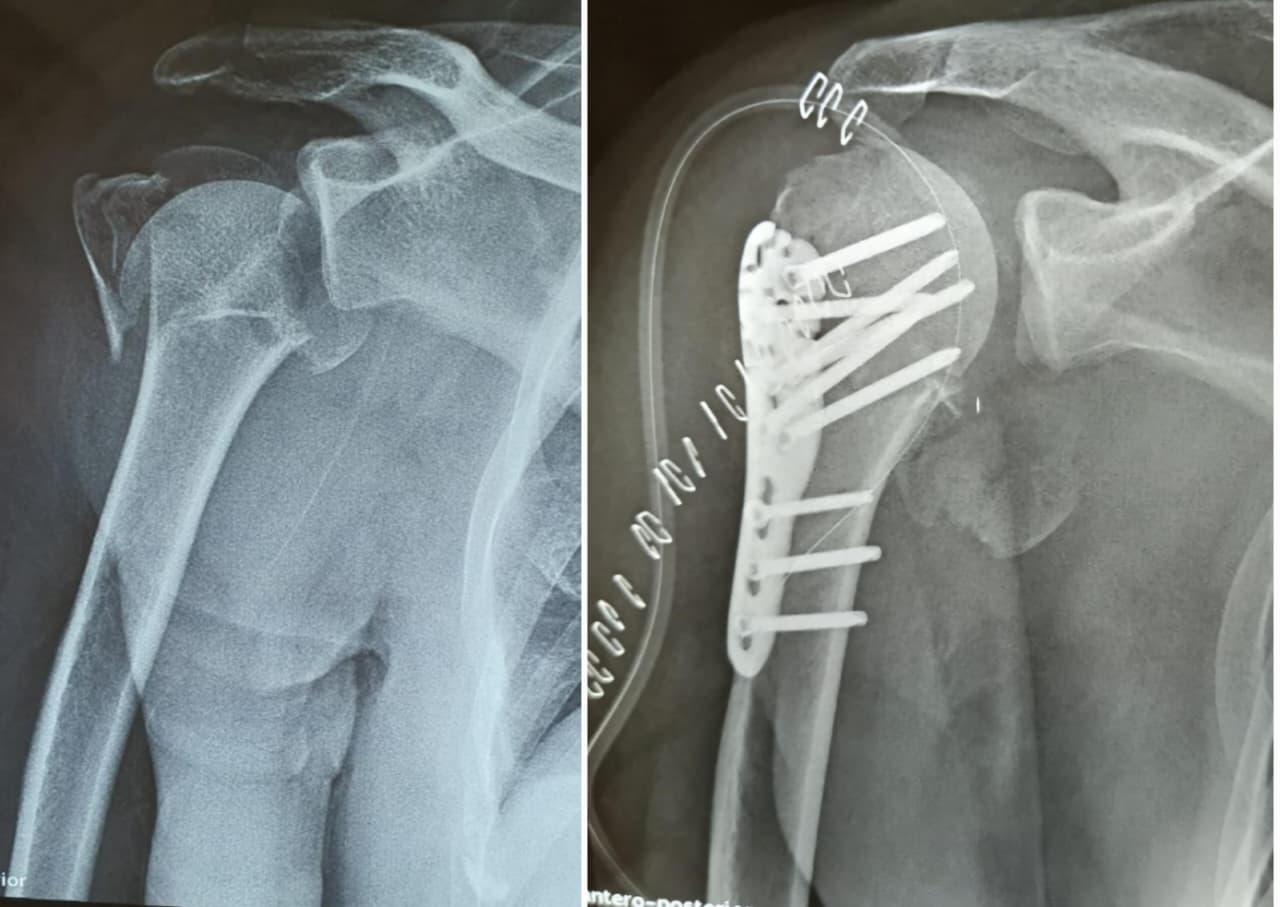

Fractures treatment